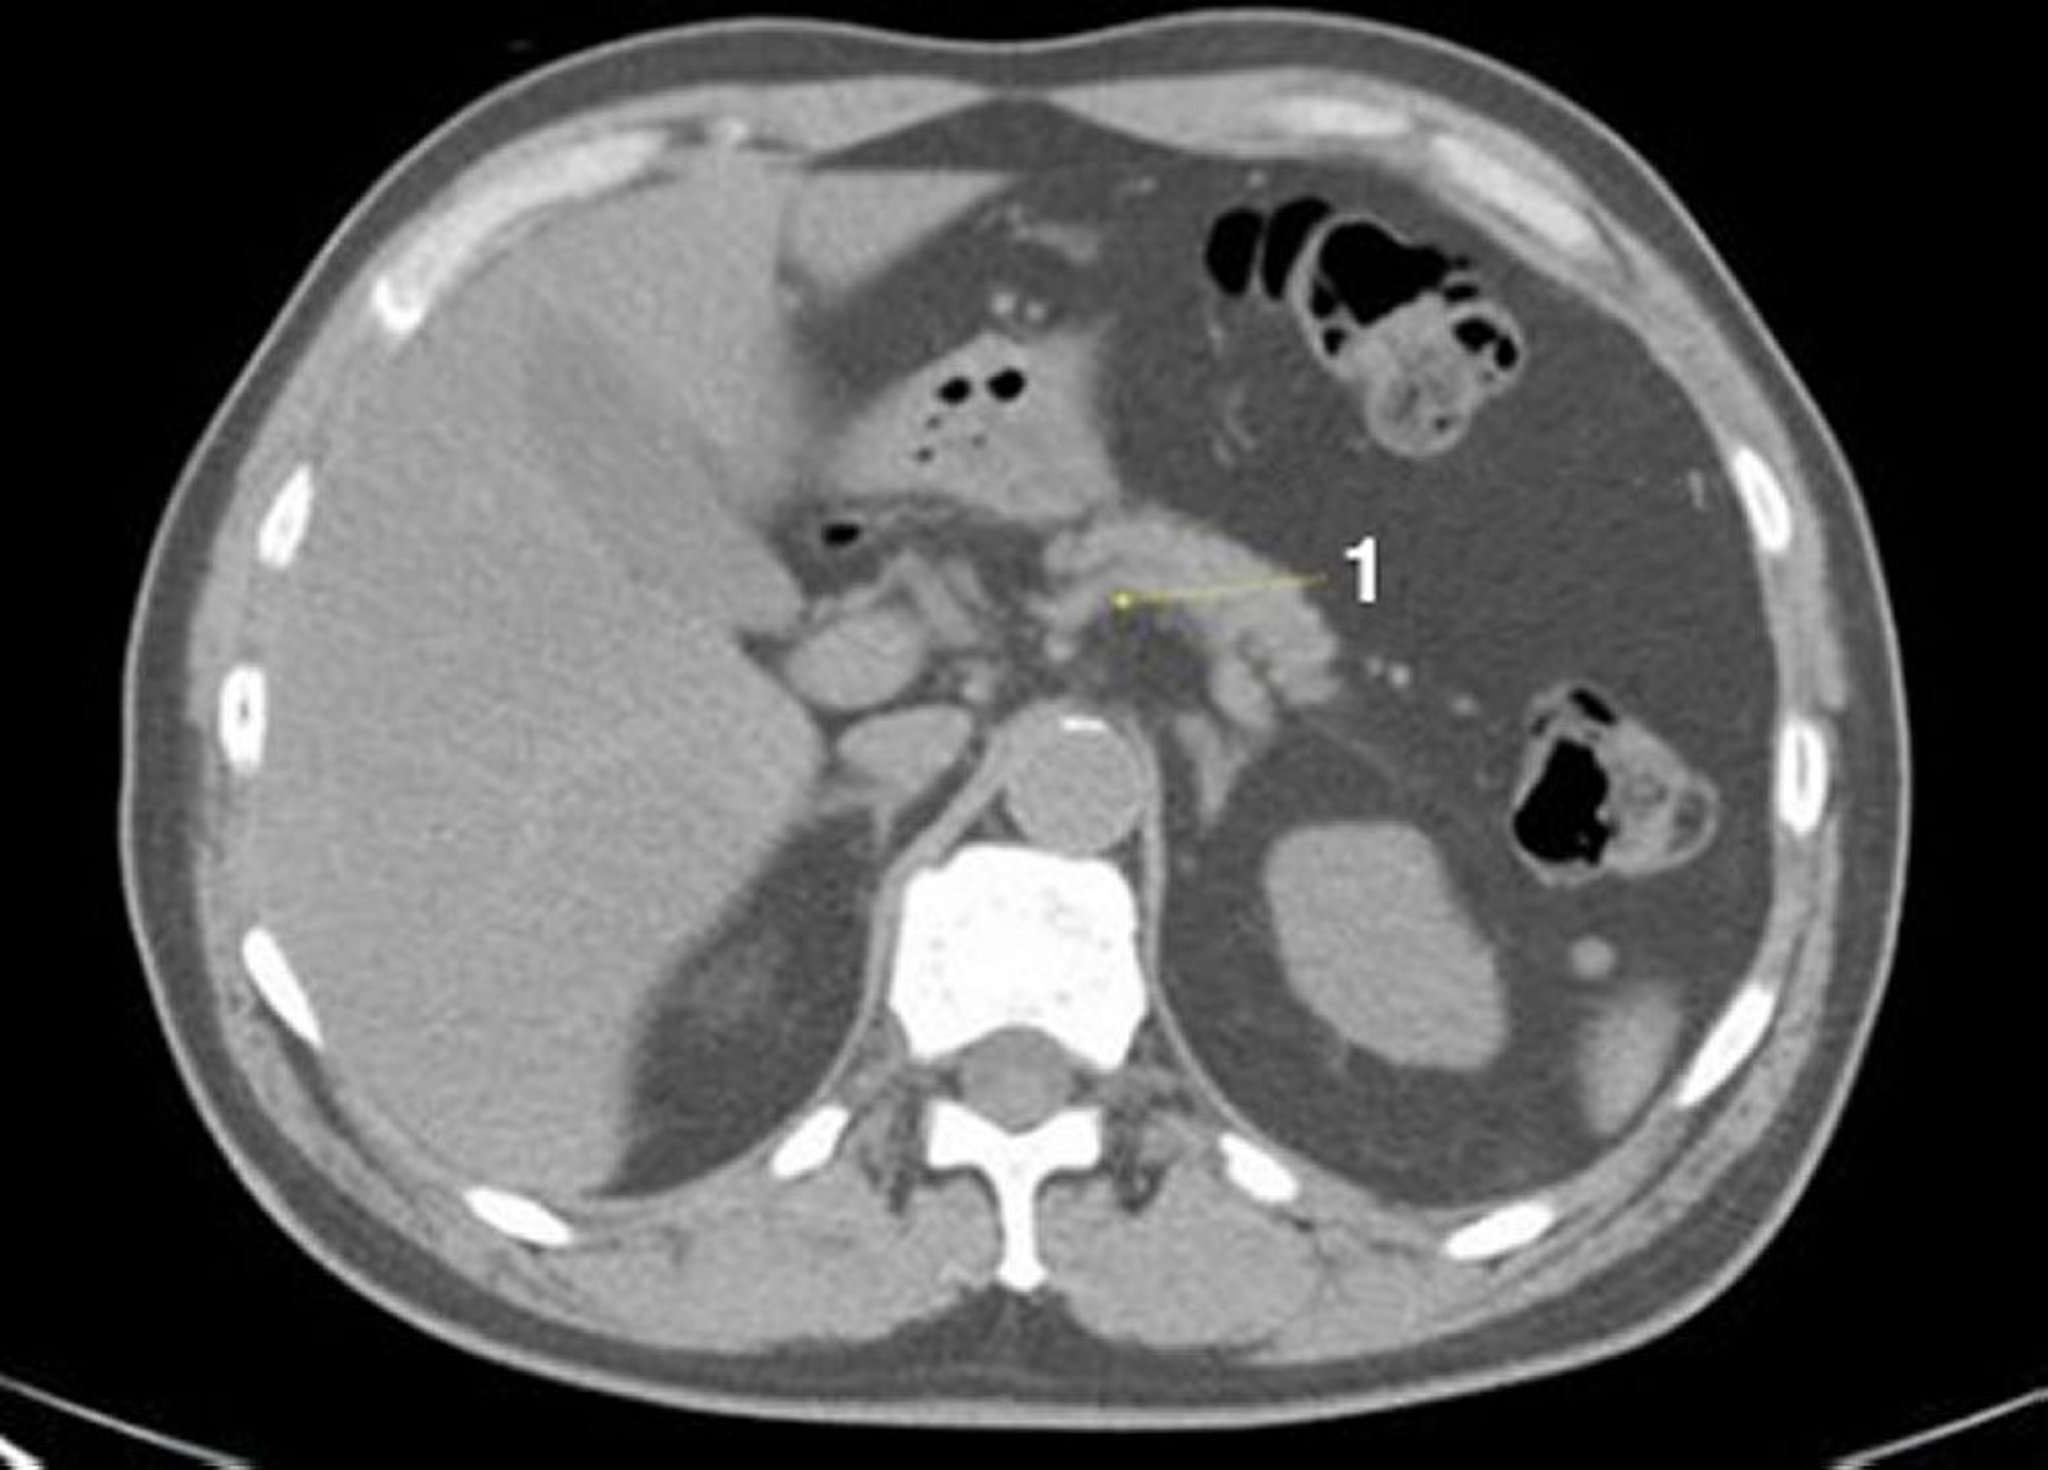

CT-Scan von Abdomen und Becken mit normaler Anatomie ohne Kontrastmittel (Folie 7)

1 = Milzvene